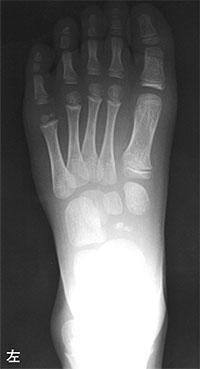

6

理学療法士実地問題 -

第51回 午前

重要度:標準

6歳の男児。1か月前から左足部痛を訴えた。エックス線写真を示す。最も考えられるのはどれか。

1

Sever病

2

舟状骨骨折

3

Freiberg病

4

足根骨癒合症

5

第1Köhler病